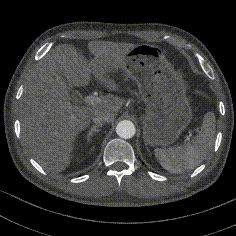

案例三(梯形瘤颈):3年前肾结石,在治疗复查过程中发现腹主动脉瘤。

案例四(梯形瘤颈):因下肢髋部疼痛行腰椎检查时发现腹主动脉瘤,进一步CTA认证确诊为腹主动脉瘤。

案例五:查体发现腹主动脉,行CTA确认腹主动脉瘤伴血栓形成。